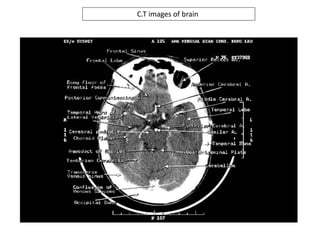

C.T images of brain